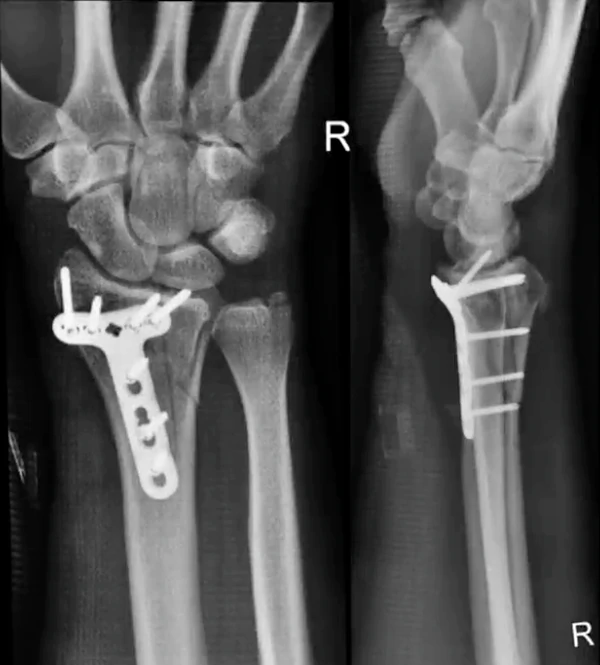

"Con el impacto de la caída (a casi 80 kilómetros por hora), mi muñeca derecha sufrió una fractura distal fragmentada del radio, que requirió cirugía", escribe en sus comentarios al final del video en Youtube. "Me instalaron una placa de titanio y siete tornillos, y me dieron de alta la tarde siguiente".